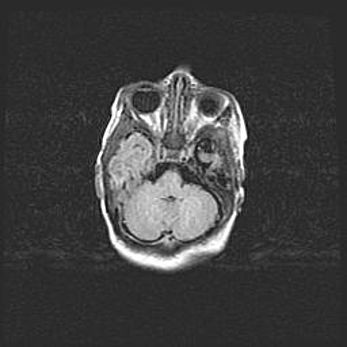

Наружная гидроцефалия с возможной атрофией височных областей.

Возраст: 28 дней

Вес: 3670 г

Пол: мужской

Окружность головы: 38 см

Срок гестации: 40 недель

Гидроцефалия головного мозга у новорожденных – это заболевание, которое характеризуется скоплением избыточного количества спинномозговой жидкости в желудочковой системе головного мозга в результате затруднения её перемещения от места выработки к месту поглощения в кровеносную систему или вследствие нарушения абсорбции. При открытой наружной форме гидроцефалии у новорожденных расширяются и переполняются субарахноидные пространства.

При нормотензивных  формах,  которые,  как  правило,  являются  следствием  перенесенных ишемических  повреждений  паренхимы  мозга,  возможно  сочетание микроцефалии  с нормотензивной гидроцефалией. В основе данных изменений лежит атрофия больших полушарий с преимущественной  локализацией  в  лобно-височных  областях.